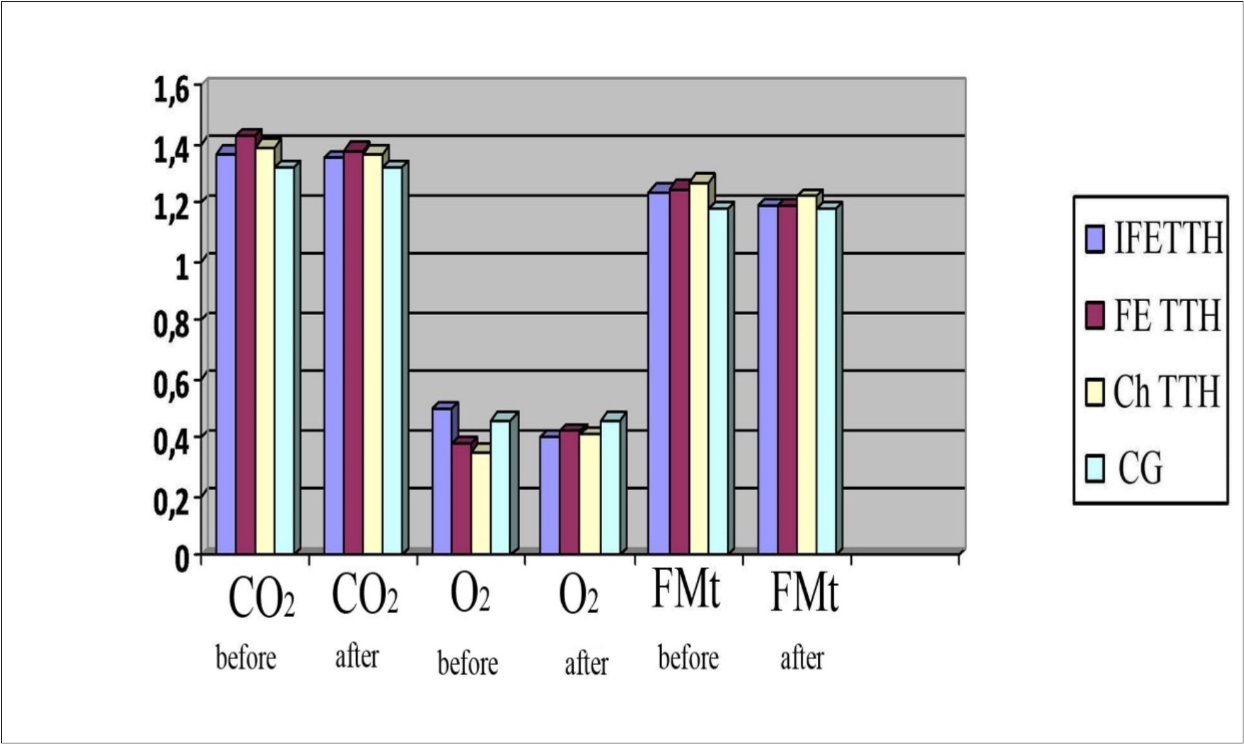

In patients with TTH, hyper-responsiveness to hypercapnic test was detected: RcCO2 was 1.43±0.05 in the group with FE TTH; 1.39±0.07 in the group of Ch TTH and 1.37±0.04 in the group of IFE TTH, which indicates a tendency for the tension of the vasodilator regulation mechanism even in clinically insignificant forms of TTH. In the study of reactivity to the O2-test, a hyporeactive response was observed in the groups with FE TTH and Ch TTH (0.38±0.04 and 0.35±0.05), respectively (Figure 3). As can be seen from Figure 3, in all groups, the reactivity coefficient (Rc) when performing functional tests using CO2 and FMt was significantly higher than using O2 (P <0.001).

Figure 3.Parameters of reactivity coefficient (Rc) to the CO2, O2 and FMt test in a patients with TTH.

The results of Phenibut on vascular reactivity parameters are shown in figure 10. To a greater extent, the effect of the drug was manifested at the initially increased RcFMt and RcCO2. A decrease in initially elevated RcCO2 was noted in all clinical groups: from 1.43±0.05 to 1.38±0.04 in patients with FE TTH; from 1.39±0.05 to 1.37±0.06 in patients with ChTTH and from 1.37±0.04 to 1.35±0.05 in patients with IFE TTH. RcFMt decreased from 1.24±0.03 to 1.19±0.02 in patients with IFETTH and from 1.25±0.04 to 1.19±0.02 in patients with FETTH (almost reaching normal values). RсCO2 also decreased in patients with ChTTH - from 1.39 ± 0.07 to 1.37 ± 0.04 - almost to normal values.

Figure 10.Dynamics of RcCO2, RcO2 and RcFMt in a patients with TTH during treatment with Noofen